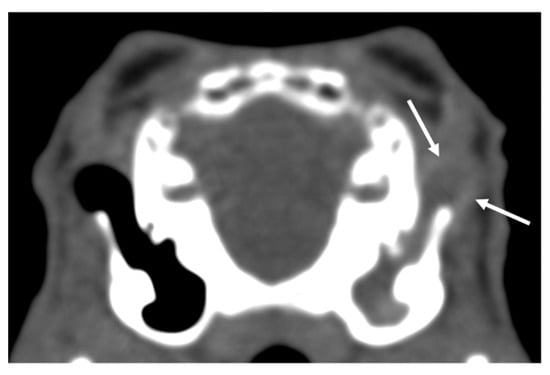

| Soft tissues | Diffuse swelling (1/1) | Solid space occupying lesion (0/0) | Cavernous space occupying lesion (0/1) | Mineralization (11/0) |